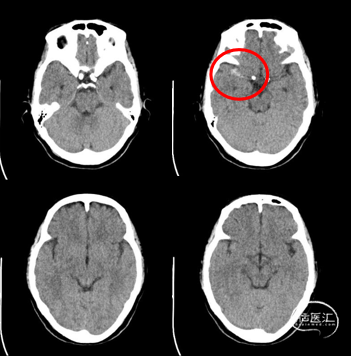

D1

2022-2-22